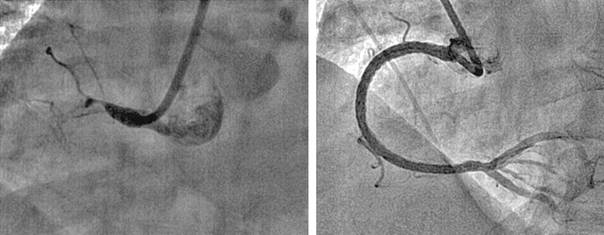

4. Суперселективная эмболизация или тромбирование АВМ. (N-бутилцианоакрилат (Hystoacryl) + жирорастворимое контрастное вещество). Рис.1.

![]() |

Рис.1 Ангиограмма больной с аневризмой левой височной доли до операции. |

Контрольная ангиограмма той же больной после эмболизации |